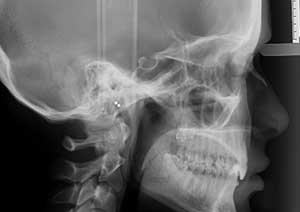

La supraclusion est définie comme le recouvrement excessif des incisives mandibulaires (inférieures) par les incisives maxillaires (supérieures).

Cliniquement, cela signifie qu’au sourire, le patient ne laisse pas apparaître les dents inférieures.

Il s’agit d’un problème de dimension verticale, fréquemment rencontré en pratique orthodontique quotidienne.

Avant

Radiographie avant